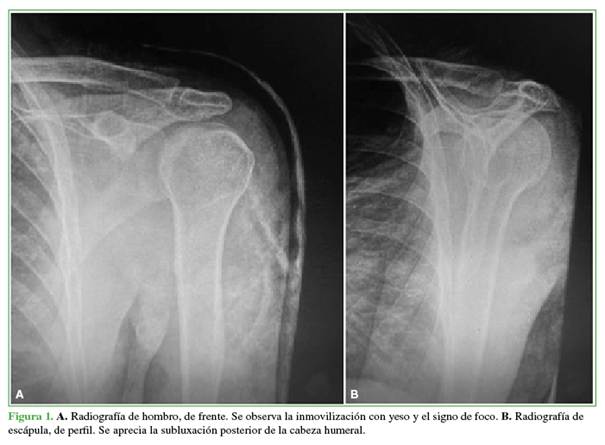

Los criterios de inclusión fueron: luxaciones agudas reducidas en la Guardia, tratamiento de la inestabilidad dentro de la segunda y tercera semana del episodio, lesión de Bankart invertida, lesión de Hill-Sachs invertida que comprometiera hasta el 30% de la cabeza humeral (Figuras 1 y 2).